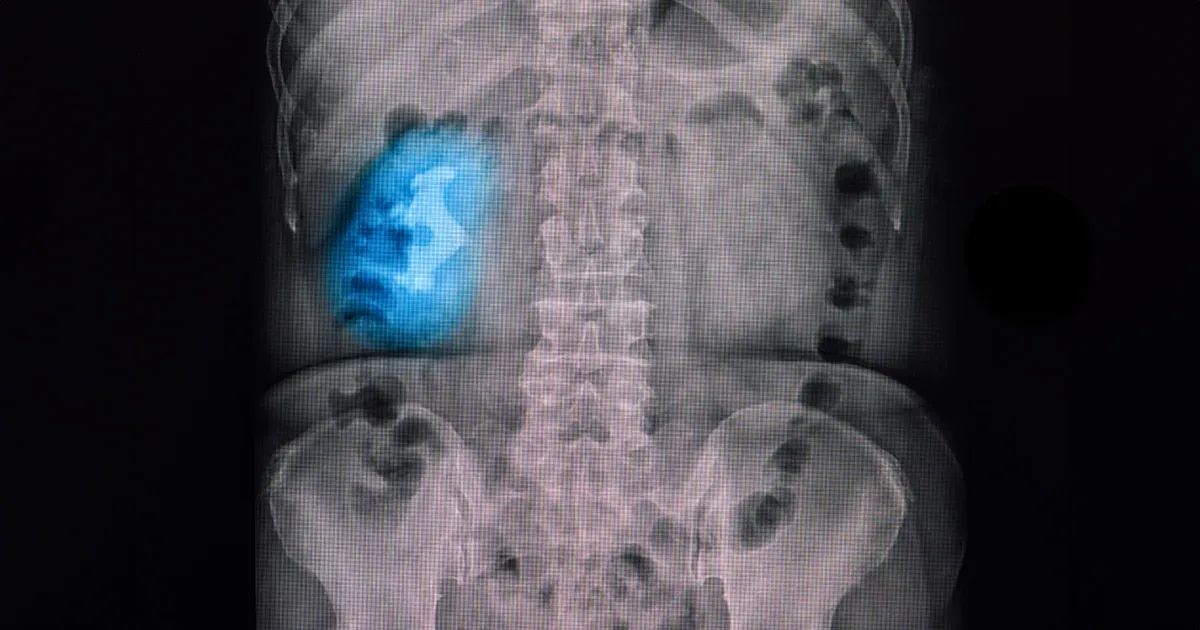

Existen cuatro tipos principales de cálculos renales: los de oxalato de calcio, los de ácido úrico, los de estruvita y los de cisteína. Entre ellos, los cálculos de estruvita tienen el aspecto más particular, ya que se forman en grandes estructuras ramificadas que se conocen como "cálculos coraliformes", que llenan los espacios internos del riñón.2

Los cálculos coraliformes o "en asta de ciervo", reciben ese nombre por su forma característica que se asemeja a un coral o "asta"; se componen sobre todo de estruvita (fosfato de amonio y magnesio) y suelen formarse a causa de infecciones crónicas del tracto urinario (ITU), en especial por bacterias que producen la enzima ureasa, como la Proteus mirabilis. Esta enzima descompone la urea, lo que aumenta la concentración de amoníaco en la orina, eleva su pH y crea un entorno alcalino favorable para que se formen cálculos.3

La anatomía de los cálculos coraliformes complica el tratamiento. Se ramifican en la pelvis renal, una zona del riñón en forma de embudo que canaliza la orina hacia los uréteres y que la llevan a la vejiga para almacenarla. Si la pelvis renal o los uréteres están bloqueados, se inflaman los riñones. Estos cálculos también pueden obstruir los cálices, donde inicia la recolección de orina. La inflamación de estas zonas, que se denomina caliectasia, provoca insuficiencia renal si no se administra algún tratamiento, por lo que es importante diagnosticar y tratar esta condición lo antes posible.7,8

Estas condiciones metabólicas, en combinación con unos malos hábitos alimenticios o la deshidratación, aumentan las probabilidades de que se formen cálculos. Para diagnosticar cálculos coraliformes, es necesario realizar un análisis de orina y pruebas de imagen para evaluar tanto la presencia de los cálculos como la infección. Un análisis de orina comprueba la presencia de bacterias y niveles elevados de pH, que son indicadores claros de cálculos relacionados con infecciones. Las imágenes que se obtienen mediante radiografías, ecografías o tomografías computarizadas revelan la forma, el tamaño y la ubicación del cálculo dentro del riñón.